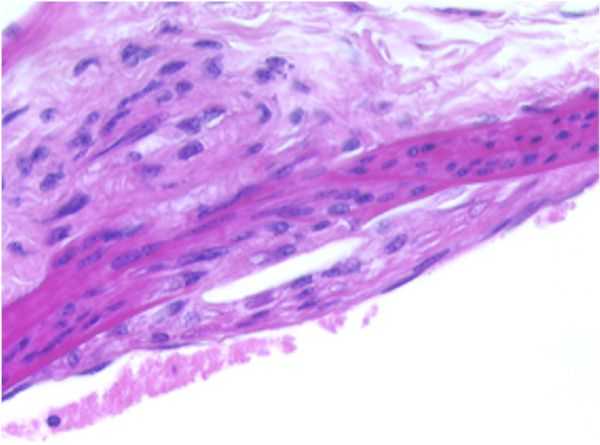

AORTA–b: F19-01

Atherosclerotic plaque, tunica intima/media, thoracic aorta.

Presented with a segment of arterial wall that exhibits a mild, focally-extensive compression of the tunica media by opposing accumulations of eosinophilic, foamy, or lipid appearing material situated within the subendothelial space of the tunica intima and the tunica adventitia. An early, minimal to mild fibroplasia is evident in these areas within both the tunica intima and tunica adventitia. The endothelium is elevated by this material occupying the subendothelial space.